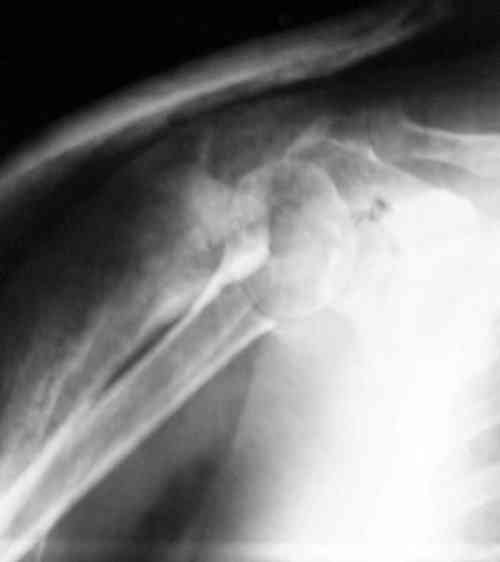

Судя по снимкам головка ротирована,успех закрытой репозиции, на мой взгляд, сомнителен, надо оперировать.

Судя по Р-граммам имеется оскольчатый перелом головки плеча. Во время открытой репозиции имеется большой риск "развалить" перелом, что значительно ухудшит кровоснабжения отломков. А так, на мой взгляд контакт м\у отломками достаточный, не смотря на наличие ротационного смещения головки думаю лучше продолжать консерватикное лечение. С уважением.

Судя по снимкам еще имеется перелом головки плеча, и чрезкостный отрыв вращательной манжеты. Для уточнения характера перелома не иешало бы сделать КТ. Если вести консервативно, то после сращения перелома будет ограничение движений в суставе не устраивающее больную. Я склоняюсь к оперативному лечению( накостный остеосинтез Т- Г образная пластина, лучше LCP для проксимальног плеча, обязательно подшить на место манжету).

В соответствии с работами Neer данный перелом можно классифицировать как однофрагментарный, так как нет диастаза более 1 см и углового смещения более 45 градусов - такие переломы лечатся консервативно. Рентген контроль каждые 10 дней- если смещение не увеличивается, то через 3-4 недели разработка движений в суставе

Уважаемый Сергей! Вы правильно написали критерии, но недооценили степень смещения в переломе хирургической шейки. Посмотрите ещё раз, это Two part fracture.